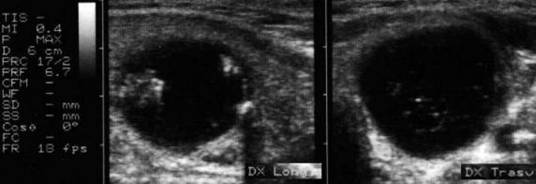

Femeie 17 ani. Voluminoasa tumefactie (32x40x45mm, 29 cc) in lobul stang, intens hipoecogena, cu echo densitati in interior, intarire posterioara. Deviatia tracheei spre dreapta.

Examen citologic; chist coloid

Aceeasi pacienta in timpul si dupa citoaspiratie